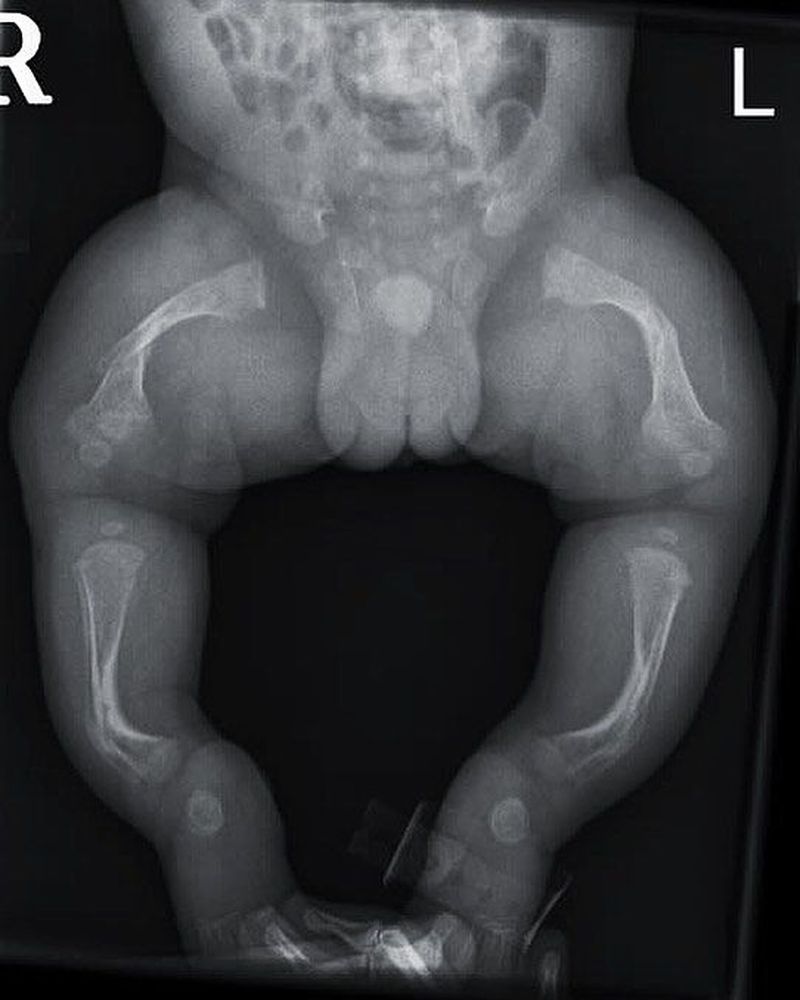

Born with soft bones! This is a neonatal frontal X-Ray of the pelvis and lower extremities demonstrating bowing of the femurs and tibias osteogenesis imperfecta! All bones are over-transparent suggesting osteopenia. Long bones are deformed due to muscles growth, which osteopenia cannot correct. Multiples fractures of different ages are seen. Osteogenesis imperfecta (OI) or Brittle Bone Disease is a congenital, genetic, connective tissue disorder caused by type I collagen gene mutation. In bone, type I collagen contributes to tensile and torsional strength. Therefore, patients with osteogenesis imperfecta have decreased bone strength and flexibility that results in frequent fractures from minor trauma. The hallmark feature is osteoporosis and fragile bones that fracture easily, as well as, joint hypermobility due to type I collagen defects in tendons and ligaments, blue sclera (from scleral thinning causing visualisation of underlying vessels), dental fragility or dentinogenesis imperfecta (discoloured teeth due to dentin exposure), and hearing loss (from dislocation or fracture of the ossicles). Clinical symptoms are highly variable, ranging from a mild form with no deformity, normal stature, and few fractures to a form that is lethal during the perinatal period. The pathology is a disturbance in the synthesis of type I collagen, which is the predominant protein of the extracellular matrix of most tissues. In bone, this defect results in osteoporosis, thus increasing the tendency to fracture. Besides bone, type I collagen is also a major constituent of dentin, sclerae, ligaments, blood vessels, and skin. With good medical management and supportive care, the majority of people who have OI will lead healthy, productive lives and can expect an average life span. Growth hormone helps growth-responsive children and treatment with bisphosphonates is aimed at increasing bone density and decreasing bone pain and fracture risk. Orthopedic surgery, physical therapy, and occupational therapy help prevent fractures and improve function. Cochlear implantation is indicated in cases of hearing loss.